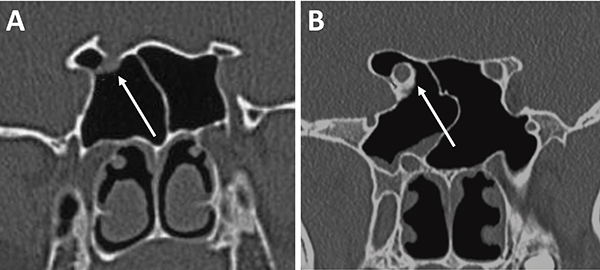

La principal utilización de la tomografía es la identificación de estructuras anatómicas óseas útiles a la hora de la planificación quirúrgica. Con una tomografía con reconstrucción 2D se pueden evidenciar con sencillas mediciones las siguientes características: septum nasal, variantes turbinales, presencia y posición de los ostiums esfenoidales, rostrum esfenoidal y su relación con el vómer, neumatización del seno esfenoidal, tabiques intrasinusales, distancia intercarotídea, grado de neumatización de etmoides posterior e identificación de nervios ópticos en su trayecto adyacente al seno esfenoidal.23,29

La evaluación del septum nasal podrá mostrar si presenta desviación o prominencias óseas que puedan dificultar el abordaje como también el tallado de un colgajo nasoseptal del lado elegido (fig. 9).[28] En caso de desvío septal se puede realizar septoplastia selectiva de la región desviada para logar un abordaje adecuado .

En referencia a las variantes turbinales se debe considerar la presencia de hipertrofia turbinal inferior y de cornetes medios bullosos (fig. 10). Ante la hipertrofia turbinal inferior será necesario realizar buena vasoconstricción preoperatoria asociada a luxofractura y lateralización para lograr un abordaje adecuado si es que no se asocia un tratamiento para la insuficiencia ventilatoria. Los cornetes medios bullosos representan una variante hipertrófica con neumatización de los mismos, los cuales podrán resecarse parcial o totalmente para lograr el correcto abordaje.

Figura 9: Desvío septal severo en TC cortes coronales. A) Inferior a fosa nasal derecha; B) Medio a fosa nasal izquierda.

Figura 10: Variantes turbinales en TC cortes coronales. A) Hipertrofia turbinal inferior (asteriscos blancos); B) Cornetes medios bullosos (asteriscos blancos) y desvío septal-espolón (flecha blanca).